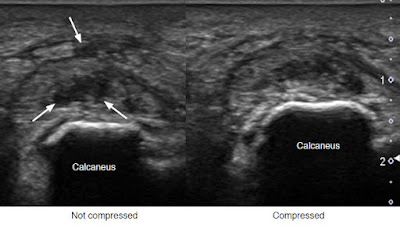

- 超音波: 正常的腳跟脂肪墊厚度為1-2公分,肪墊厚度未壓縮時小於10-12mm可以強烈懷疑(目前沒有公認標準,且變異性很大,也有研究建議<7-9mm),另外有研究以比例計算,壓縮HFP厚度/未壓縮HFP厚度如果是<0.45或>0.75為異常